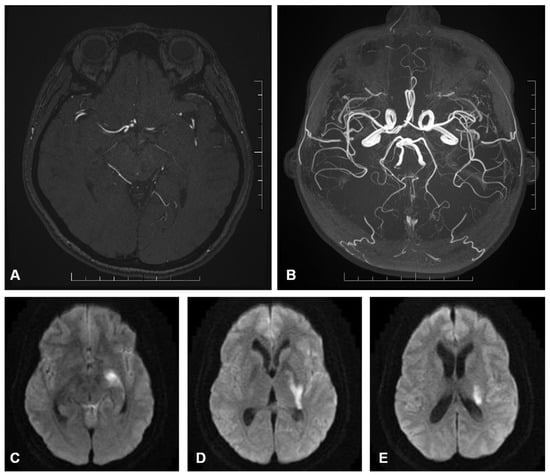

Figure 2. (A) axial image of a contrast enhanced MR intracranial angiogram which demonstrates the course of the AChoA. The artery gives rise to multiple perforators as it traverses the carotid, ambient and choroidal cisterns which may supply adjacent eloquent structures including the optic nerve, medial temporal lobe and middle cerebral peduncle. (B) axial image of a maximum intensity projection of the same contrast enhanced MR angiogram which demonstrates the path of the AChoA in relation to the anterior and posterior circulation. (CE) B1000 diffusion weighted axial images of the brain arranged caudal to cranial. These panels demonstrate restricted diffusion (hyperintensity) involving the AChoA territory in keeping with acute infarction.There is involvement of the hippocampus/mesiotemporal lobe (C), internal limb of the internal capsule encroaching on the lateral thalamus (D), and the corona radiate extending towards the caudate tail (E).

Within the endovascular cohort, one patient had an AChoA territory infarct (Figure 1) and the other had a catheter-related PCA (posterior cerebral artery) and MCA (middle cerebral artery) territory infarct. The catheter-related infarct presented with limb hemiparesis after 4 h, which resolved after 1 week.

Within the clipping cohort, both patients had AChoA territory infarcts. The post-procedural mRS were 5 and 3, respectively (Figure 2).

AChoA arises from the dorsal surface of the ICA (Internal carotid artery) in 98% of cases [4,6]. The cisternal segment traverses the carotid and ambient cisterns, where perforating arteries originate [7]. These perforators supply eloquent structures, including the optic tract, internal capsule (posterior limb, genu, and retrolenticular parts), globus pallidus, caudate tail, lateral thalamus, cerebral peduncle, hippocampus, and amygdala [8,9]. The choroidal segment traverses the choroidal fissure, entering the temporal horn to supply the choroid plexus and anastomose with the choroidal system (Figure 1).